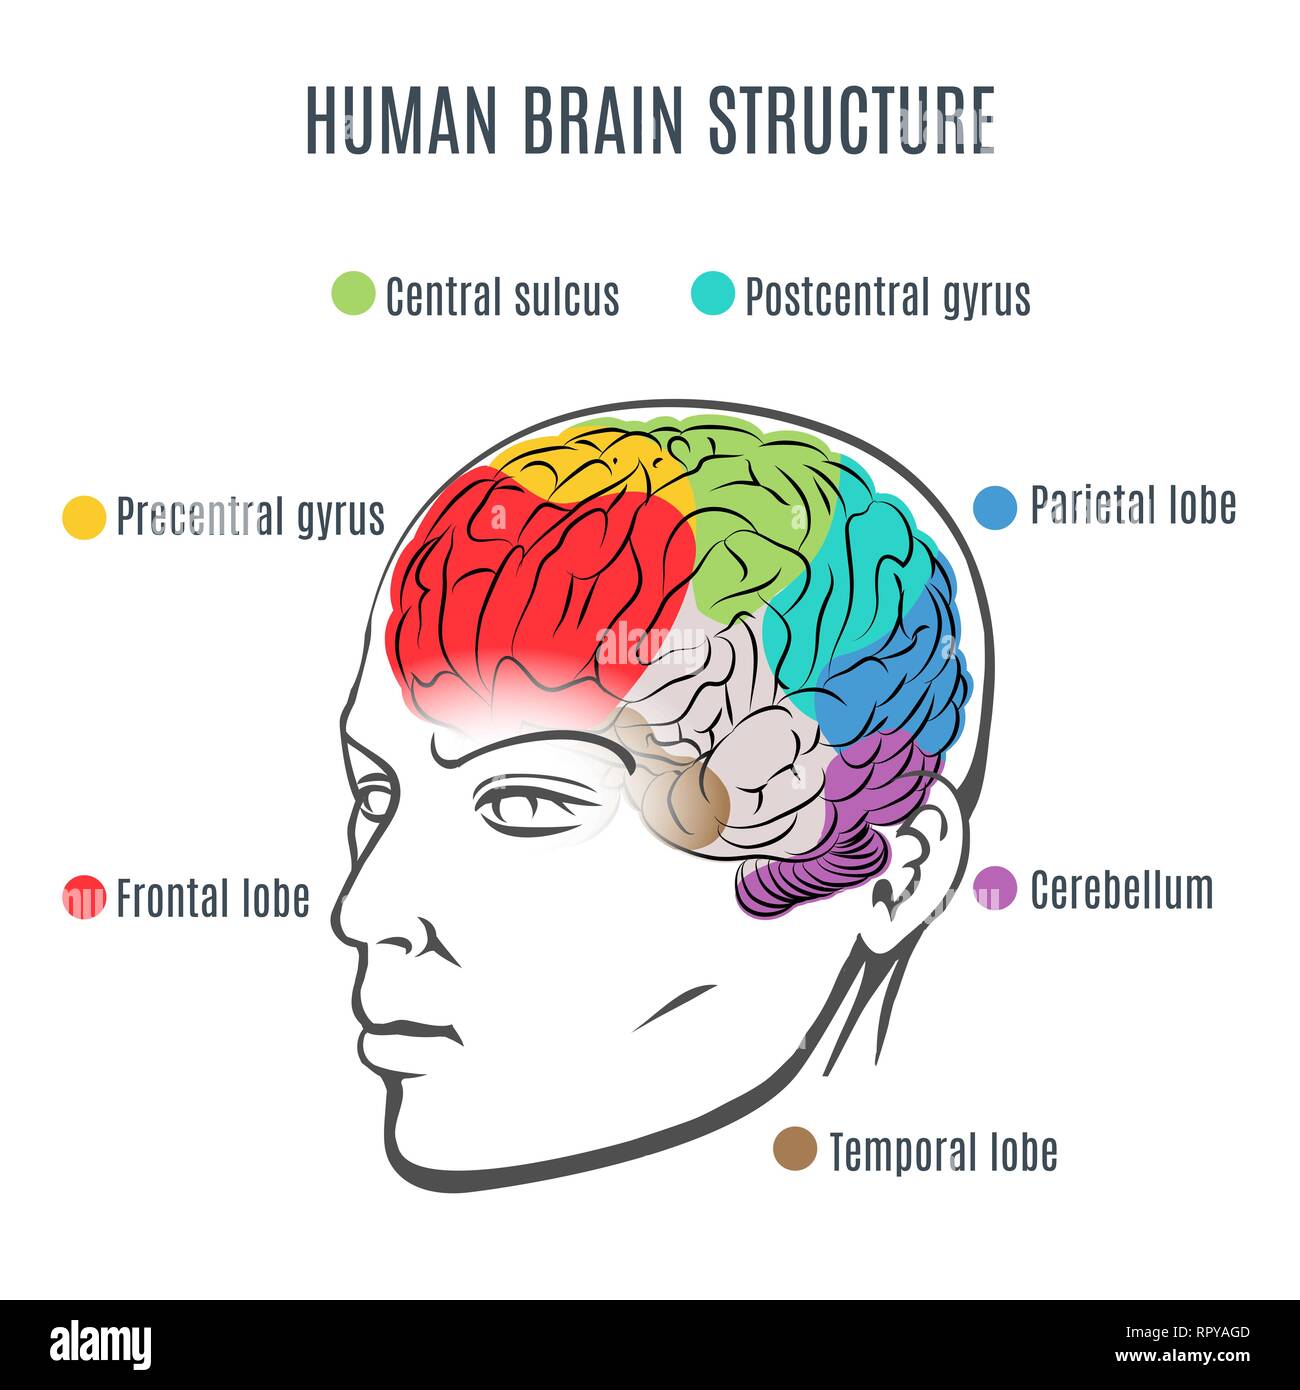

RF2R1KGAT–Struttura cerebrale umana. Emisferi e lobi della corteccia cerebrale. lobi frontali, temporali, occipitali e parietali. vista laterale e superiore

RFRPYAGD–Struttura del cervello umano. Testa umana con all'interno del cervello. Cervello umano parti principali. Illustrazione Vettoriale.

RFH7J0RH–Parti principali del cervello umano. Cervello umano nel disegno stile. Illustrazione Vettoriale